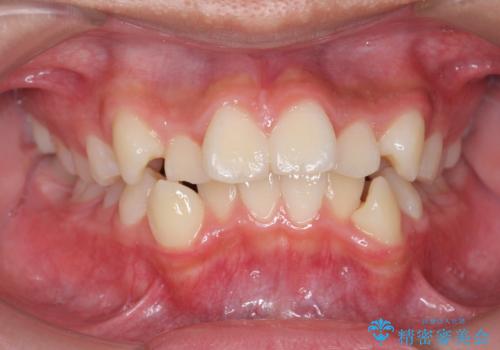

[ マウスピース矯正] 前歯のがたつき 出っ歯に見える歯をきれいに

担当医 大元洋佑

![[ マウスピース矯正] 前歯のがたつき 出っ歯に見える歯をきれいに の症例 治療前](https://seimitsushinbi.jp/wp/wp-content/uploads/2025/04/IMG_0123-500x350.jpg?v=1744960747)

![[ マウスピース矯正] 前歯のがたつき 出っ歯に見える歯をきれいに の症例 治療後](https://seimitsushinbi.jp/wp/wp-content/uploads/2025/04/a5c1eab0aff12598c7b5c9fb710c2648-500x350.jpg?v=1744960670)